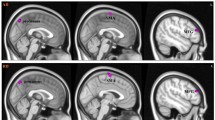

The volume of the white matter decreased significantly in ADHD patients compared with normal control subjects (P = 0.04), and the volume of the brain structures was generally smaller in ADHD patients than in control subjects except for the putamen and globus pallidus (Table 2). ADHD patients had a decrease of 9% in the volume of cerebral cortex and of 8% in the volume of caudate nucleus, though there is no significant difference with P-value 0.12 and 0.27 respectively. The visualization of statistical difference maps of the cortical thickness showed focal thinning in bilateral frontal regions and the right cingulate cortex in ADHD patients (P < 0.05, uncorrected) (Fig. 1; Table 3).

The thickness of cerebral cortex is an additional indicator of integrity of cytoarchitecture in the cortex (Luders et al. 2009; Makris et al. 2007; Shaw et al. 2006). The visualization of statistical difference maps of the cortical thickness showed focal thinning in the bilateral frontal regions and the right cingulate cortex in ADHD, which is similar to some previous studies (Makris et al. 2007; Shaw et al. 2006). Makris et al. (2007) found there was a significant cortical thinning in ADHD in a distinct cortical network supporting attention especially in the right hemisphere involving the inferior parietal lobule, the dorsolateral prefrontal, and the anterior cingulate cortices. Shaw et al. (2006) also found that children with ADHD had global thinning of the cortex, most prominently in the medial and superior prefrontal and precentral regions; children with worse clinical outcome had a thinner left medial prefrontal cortex at baseline than the better outcome group and controls. However, Wolosin et al. (2009) found only a significant decrease in cortical folding bilaterally, but no significant differences in cortical thickness were detected. And Rusch et al. (2007) found Women with BPD and comorbid ADHD had a thinner isthmus of the corpus callosum, compared with healthy women. Our results provide new insights into the difference of the cortical thickness in ADHD, revealing the selective thinning of cerebral cortex that subserves attention and executive function. Because of some limitations, the particular thinning cortical regions identified in this study should be interpreted cautiously and subjected to replication in larger samples. An important limitation of this study is the small sample size, and another is the fully automated method used in FreeSurfer software. The technique of three-D parametric surface modeling of FreeSurfer overcomes the limitations of volumetric segmentation and represents complex sulcal structures. However, errors in the cortical surface model still exist in folded regions because of the limit of the resolution in volume images, which may occasionally obscure subtle neuroanatomic effects (Devlin and Poldrack 2007; Makris et al. 2008b). On the other hand, Cortical thickness measurements suggested differences in rather small spots in the cingulate cortex and dorsolateral frontal lobe, the termination fields of decreased FA in forceps minor, internal capsule, and corona radiata are much larger showed by DTI analysis. The mismatches between the two methods could be caused by: (1) Cortical thickness measurements just focus on the cortex, but the difference of white matter (there are significant decrease of the volume of the white matter in ADHD patients) can’t display on the statistical maps of the cortical thickness. (2) DTI just focuses on the white matter and more sensitive to the FA change of the white matter. Low FA values of the white matter may reflect axonal degeneration, and/or less well-organized tracts, and may be induced by a variety of influences. (3)These affected fibers anatomically connected with the cortical areas (bilateral frontal regions and the cingulate cortex). They can influence each other, but these changes maybe are not in a synchronous manner, and it’s still unknown which is the initiator or the starter. Anyway, future studies are needed to further explore the relationships between the cortex and white matter abnormalities in this disorder.